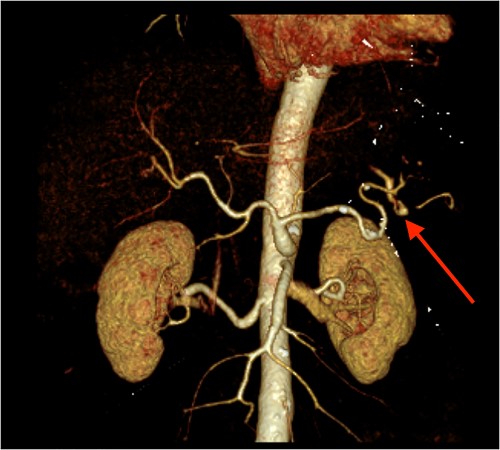

CT angiography of the abdomen with 3D reconstruction. Ruptured SAP.